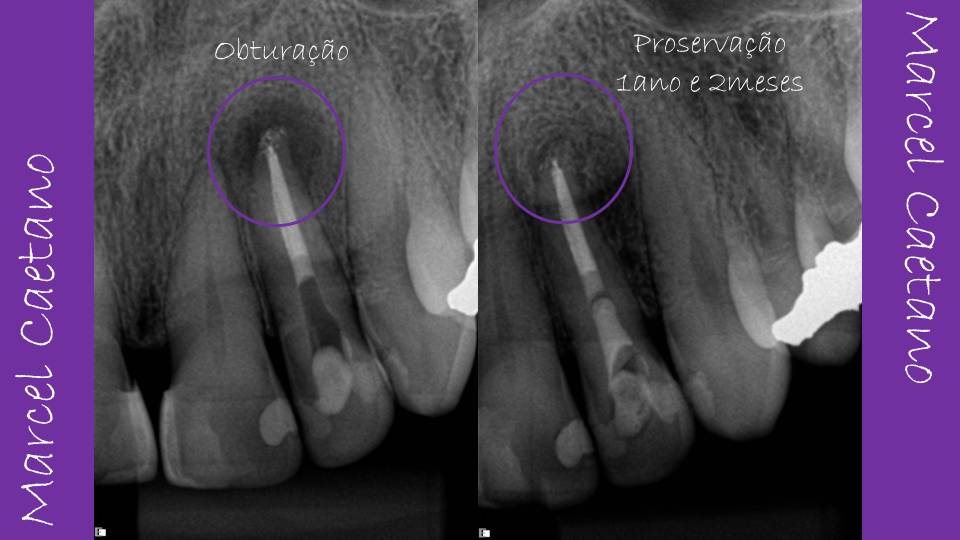

As radiografias iniciais mostravam que havia presença de desvio apical. O tratamento endodôntico anterior não respeitou a anatomia do canal/raiz, cuja curvatura apical nos sentidos distal e disto-palatino são comuns nestes dentes.

A proservação radiográfica realizada após 1 ano

e 2 meses nos mostra que ocorreu o reparo

ósseo apical, o que demonstra que os procedimentos de limpeza, modelagem

e desinfecção do canal foram alcançados com sucesso, apesar das dificuldades anatômicas impostas pela presença

do desvio apical.